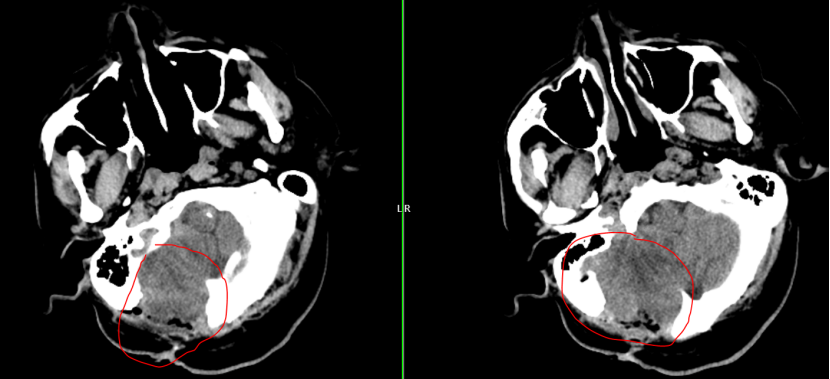

2024年初:肿瘤出现了第一次“跨界”转移。朱先生因剧烈头痛头晕入院,检查发现癌细胞由血液转移右侧小脑半球,约39mm×35mm大小,周焱峰主任带领团队为其行 显微镜下右侧小脑巨大转移瘤切除术,手术顺利完成。术后配合放化疗,病情稳定。

2025年8月:患者头晕、呕吐症状加剧,复查头颅MRI显示右侧小脑半球恶性肿瘤复发,约45mm×35mm大小,周围水肿严重,同时患者合并高血压和糖尿病,治疗难度加大。

此次手术面临诸多挑战:手术区域有疤痕和粘连,结构不清,容易出血;肿瘤位于小脑,紧邻脑干,手术中必须保护好神经功能;首次手术后部分枕骨缺失,脑组织生理结构已有改变,对手术入路设计和术中脑组织保护提出了更高要求。

面对如此棘手的局面,周焱峰主任带领团队进行详尽的术前讨论,研读MRI影像,模拟手术入路,为其量身制定手术预案和应急预案。

历时4小时,神经外科团队仔细分离粘连组织,准确找到肿瘤边界,完整切除了复发的肿瘤,术中监测平稳,最大程度地保护了神经功能。手术顺利完成,所有人都松了一口气.。